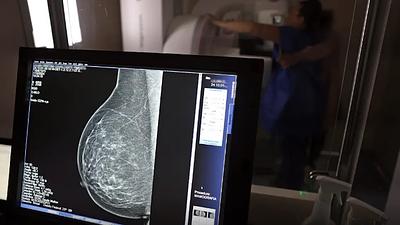

Especialistas reafirmam eficácia da mamografia para prevenir câncer de mama

Os vídeos que circulam na Internet chegam a associar a mamografia ao surgimento de câncer não apenas de mama, mas em outras partes do corpo e também como causa de inflamação e de transtornos de saúde.